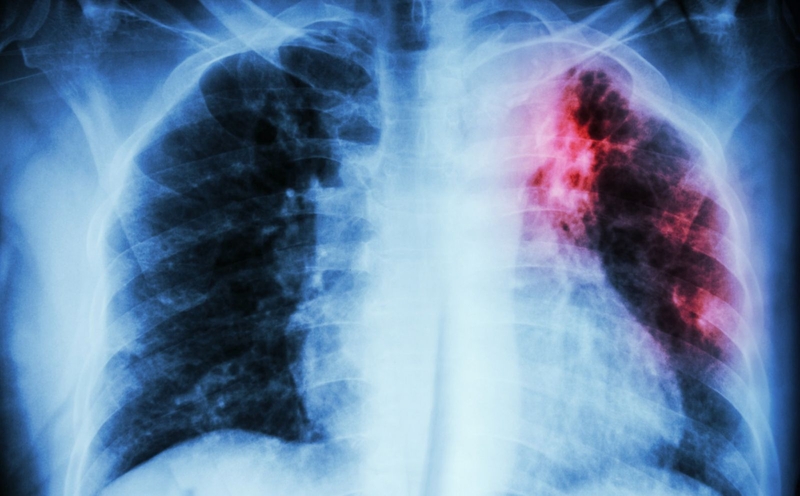

sự nguy hiểm của bệnh lao phổi Nếu không được chẩn đoán và can thiệp điều trị kịp thời, vi khuẩn lao có thể lây lan khắp cơ thể

Nếu không được chẩn đoán và can thiệp điều trị kịp thời, vi khuẩn lao có thể lây lan khắp cơ thể. Từ đó phát sinh ra hàng loạt các vấn đề ảnh hưởng đến hệ tim mạch. Không những vậy, quá trình trao đổi chất cũng như chức năng của các cơ quan khác cũng bị ảnh hưởng.

Trong một số trường hợp nghiêm trọng, bệnh lao phổi còn có nguy cơ dẫn đến tình trạng nhiễm trùng đường huyết. Đây là tình trạng nhiễm trùng rất nguy hiểm. Nó có thể đe dọa đến tính mạng người bệnh với tỷ lệ tử vong cao.